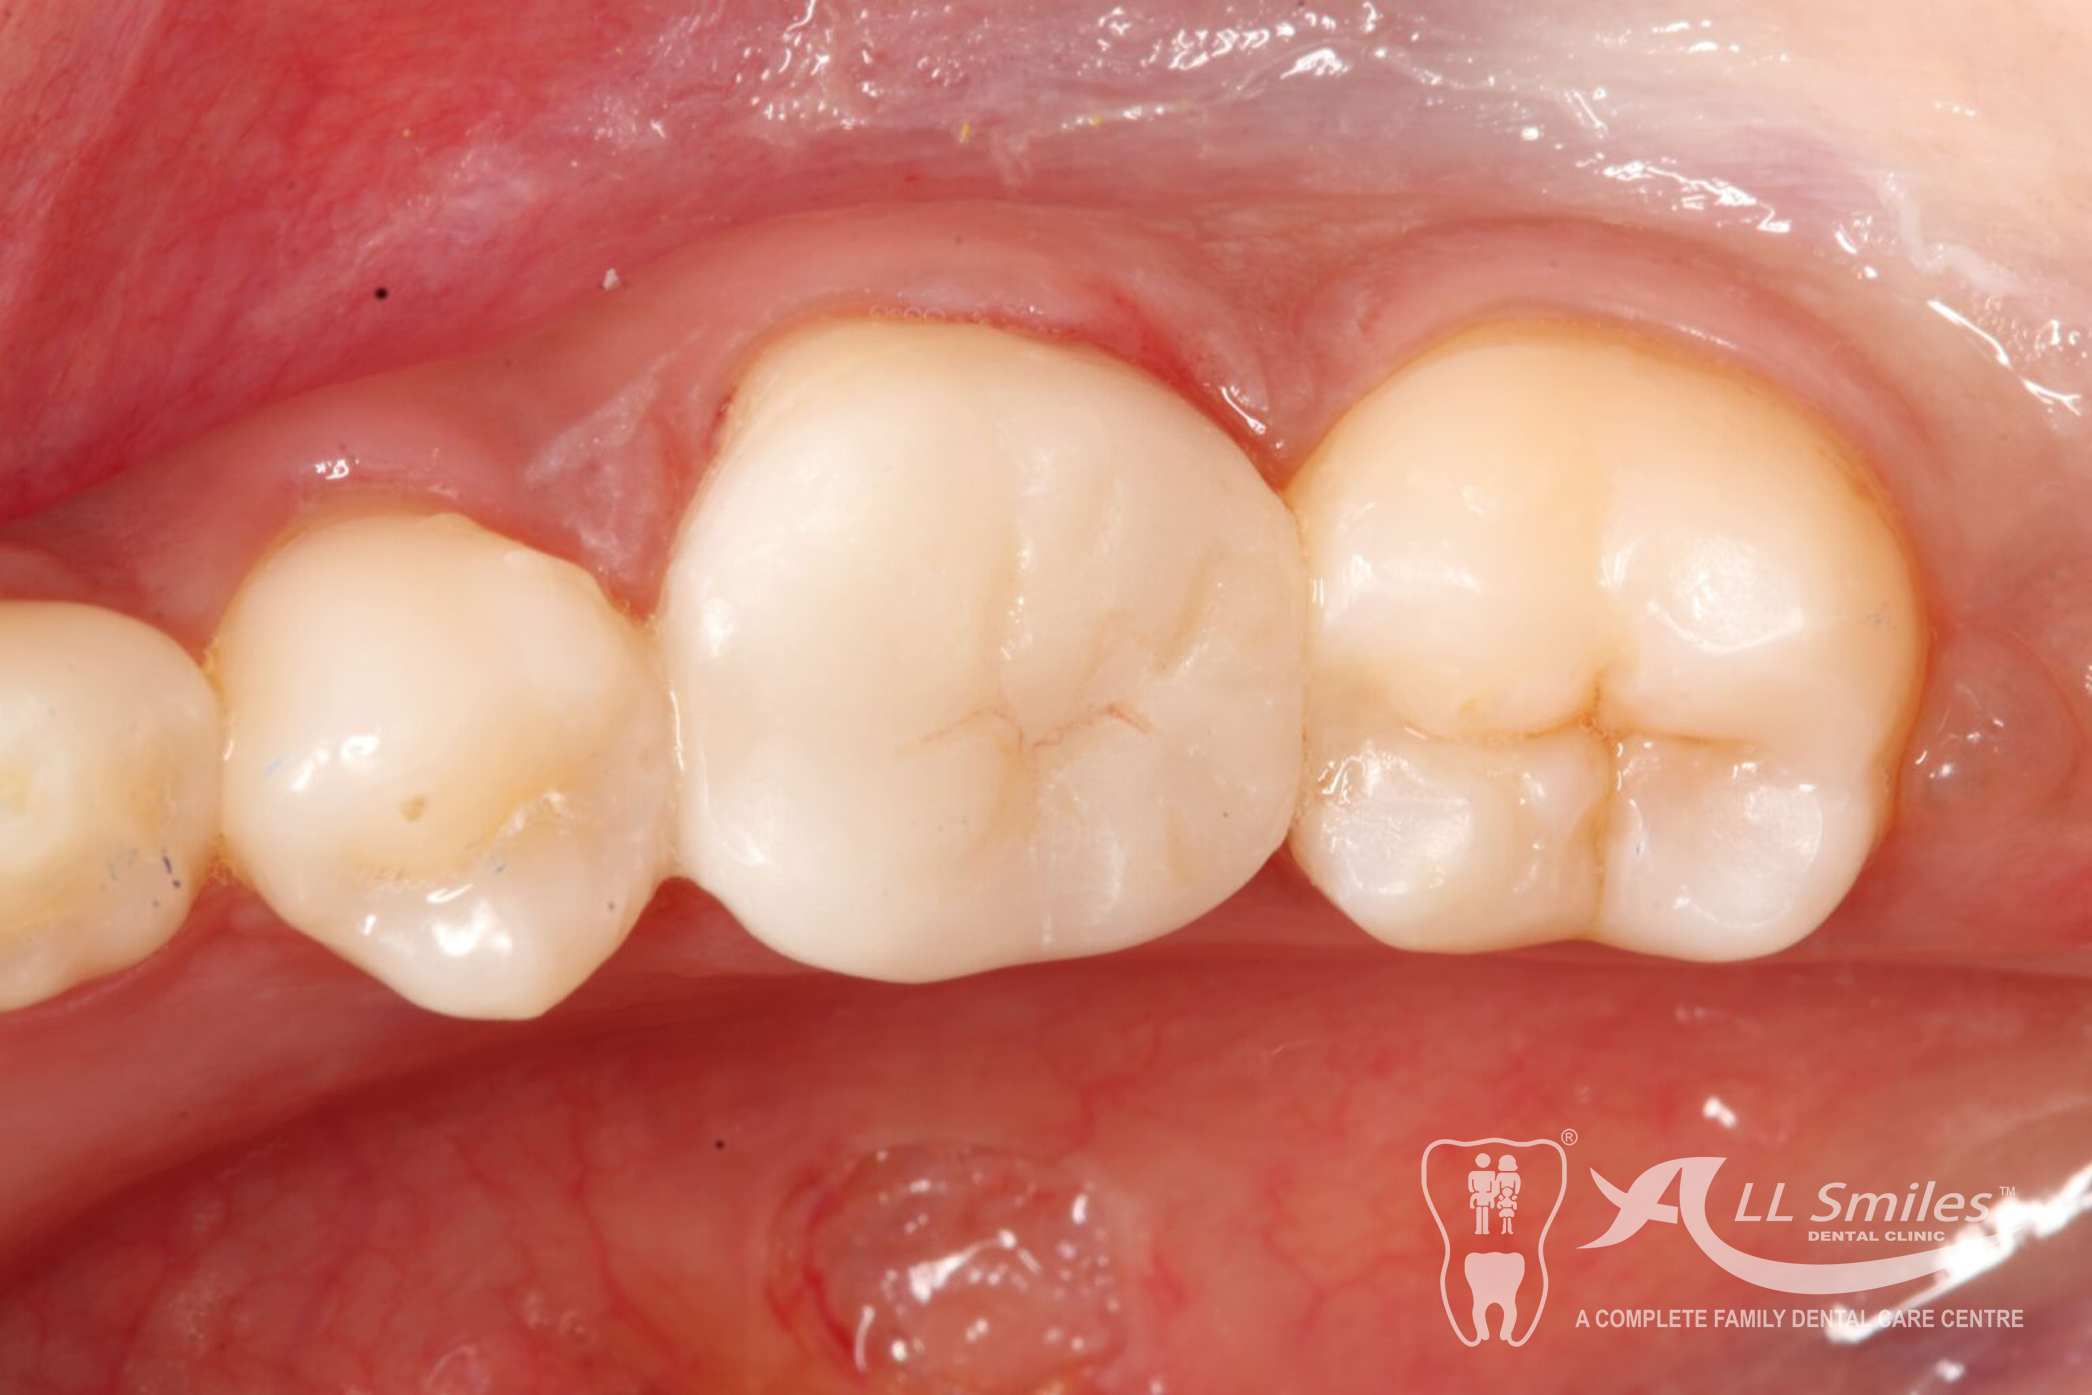

Crowns & Bridges Gallery